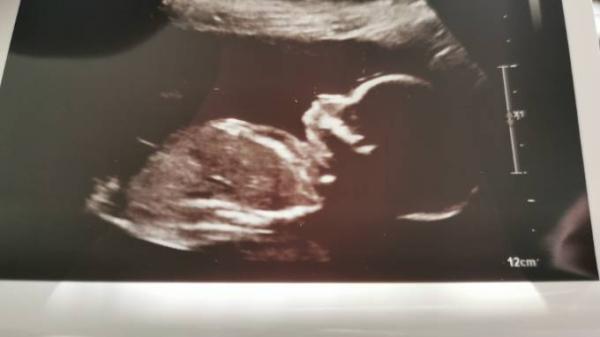

Hatte heute wieder ein Ultraschall, alles ist in bester Ordnung nur das Geschlecht konnte man nicht sehen. Habe am 08.02 ein Termin zum doppler im Krankenhaus, wird das bei jedem gemacht? Ach und ein tolles Bild gab es heute auch Liebe Grüße

Bild zu Arzttermin - Forum für Juni - Mamis